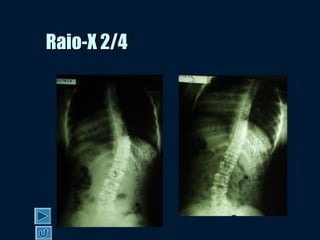

Raio-X 2/4Raio-X 2/4

Raio-X 3/4Raio-X 3/4